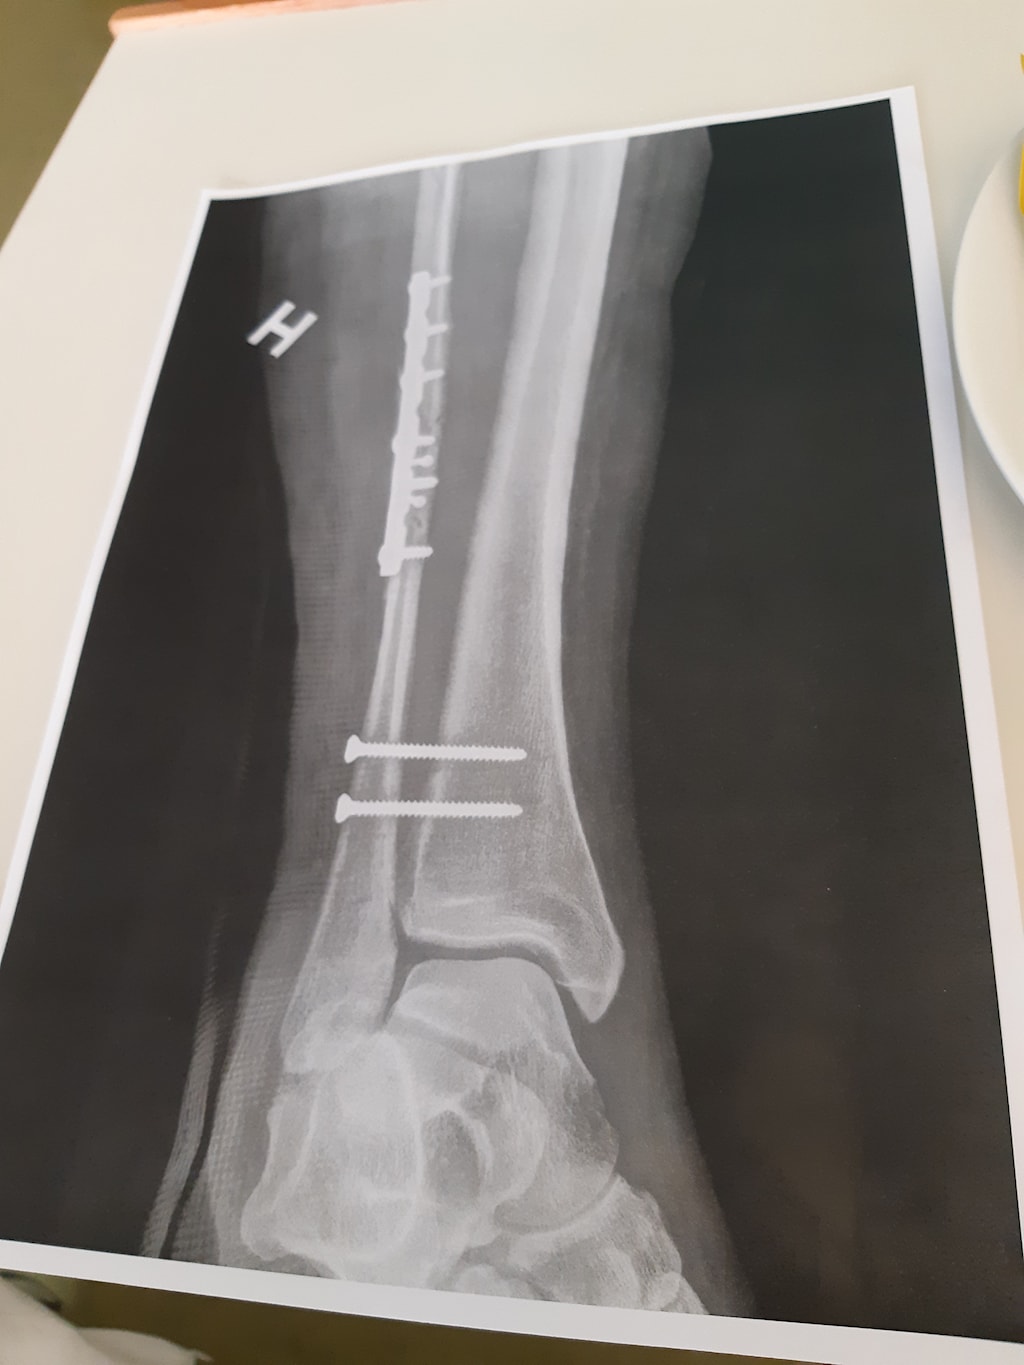

Røntgenbilder tas og viser et komplisert brudd i leggen. Altså, vi leker jo ikke beinbrudd liksom. Neida, her gjør vi det skikkelig når vi først er i gang. Her er det bare å vrenge på plass ankel og legg mens to sterke karer holder undertegnede nede og i ro og slenge på en midlertidig gips for transport videre til akuttmottaket Haukeland. Det fylles på med min beste venn, Mr. Morfin.

Onsdagen kommer og jeg sovner tungt på operasjonsbenken. Våkner etter noen gode timer i drømmeland med ny fin gips og 10 flotte skruer i legg og ankel. Mer morfin og jeg føler meg dødsbra! Kirurgen kommer på besøk og skryter over den fantastiske jobben de har gjort og jeg gliser fra øre til øre.

De neste dagene går. Smerten øker på i takt med trykket i foten. Gipsen er tatt av og foten blir større og større. Det tas en trykktest som viser høye tall på et punkt og litt lavere på et punkt. Resultatet kommer lørdagen og heter Compartment Syndrome. Får vite at jeg heldig hvis jeg har muskler og nerver igjen i ankelen, som faktisk fungerer.